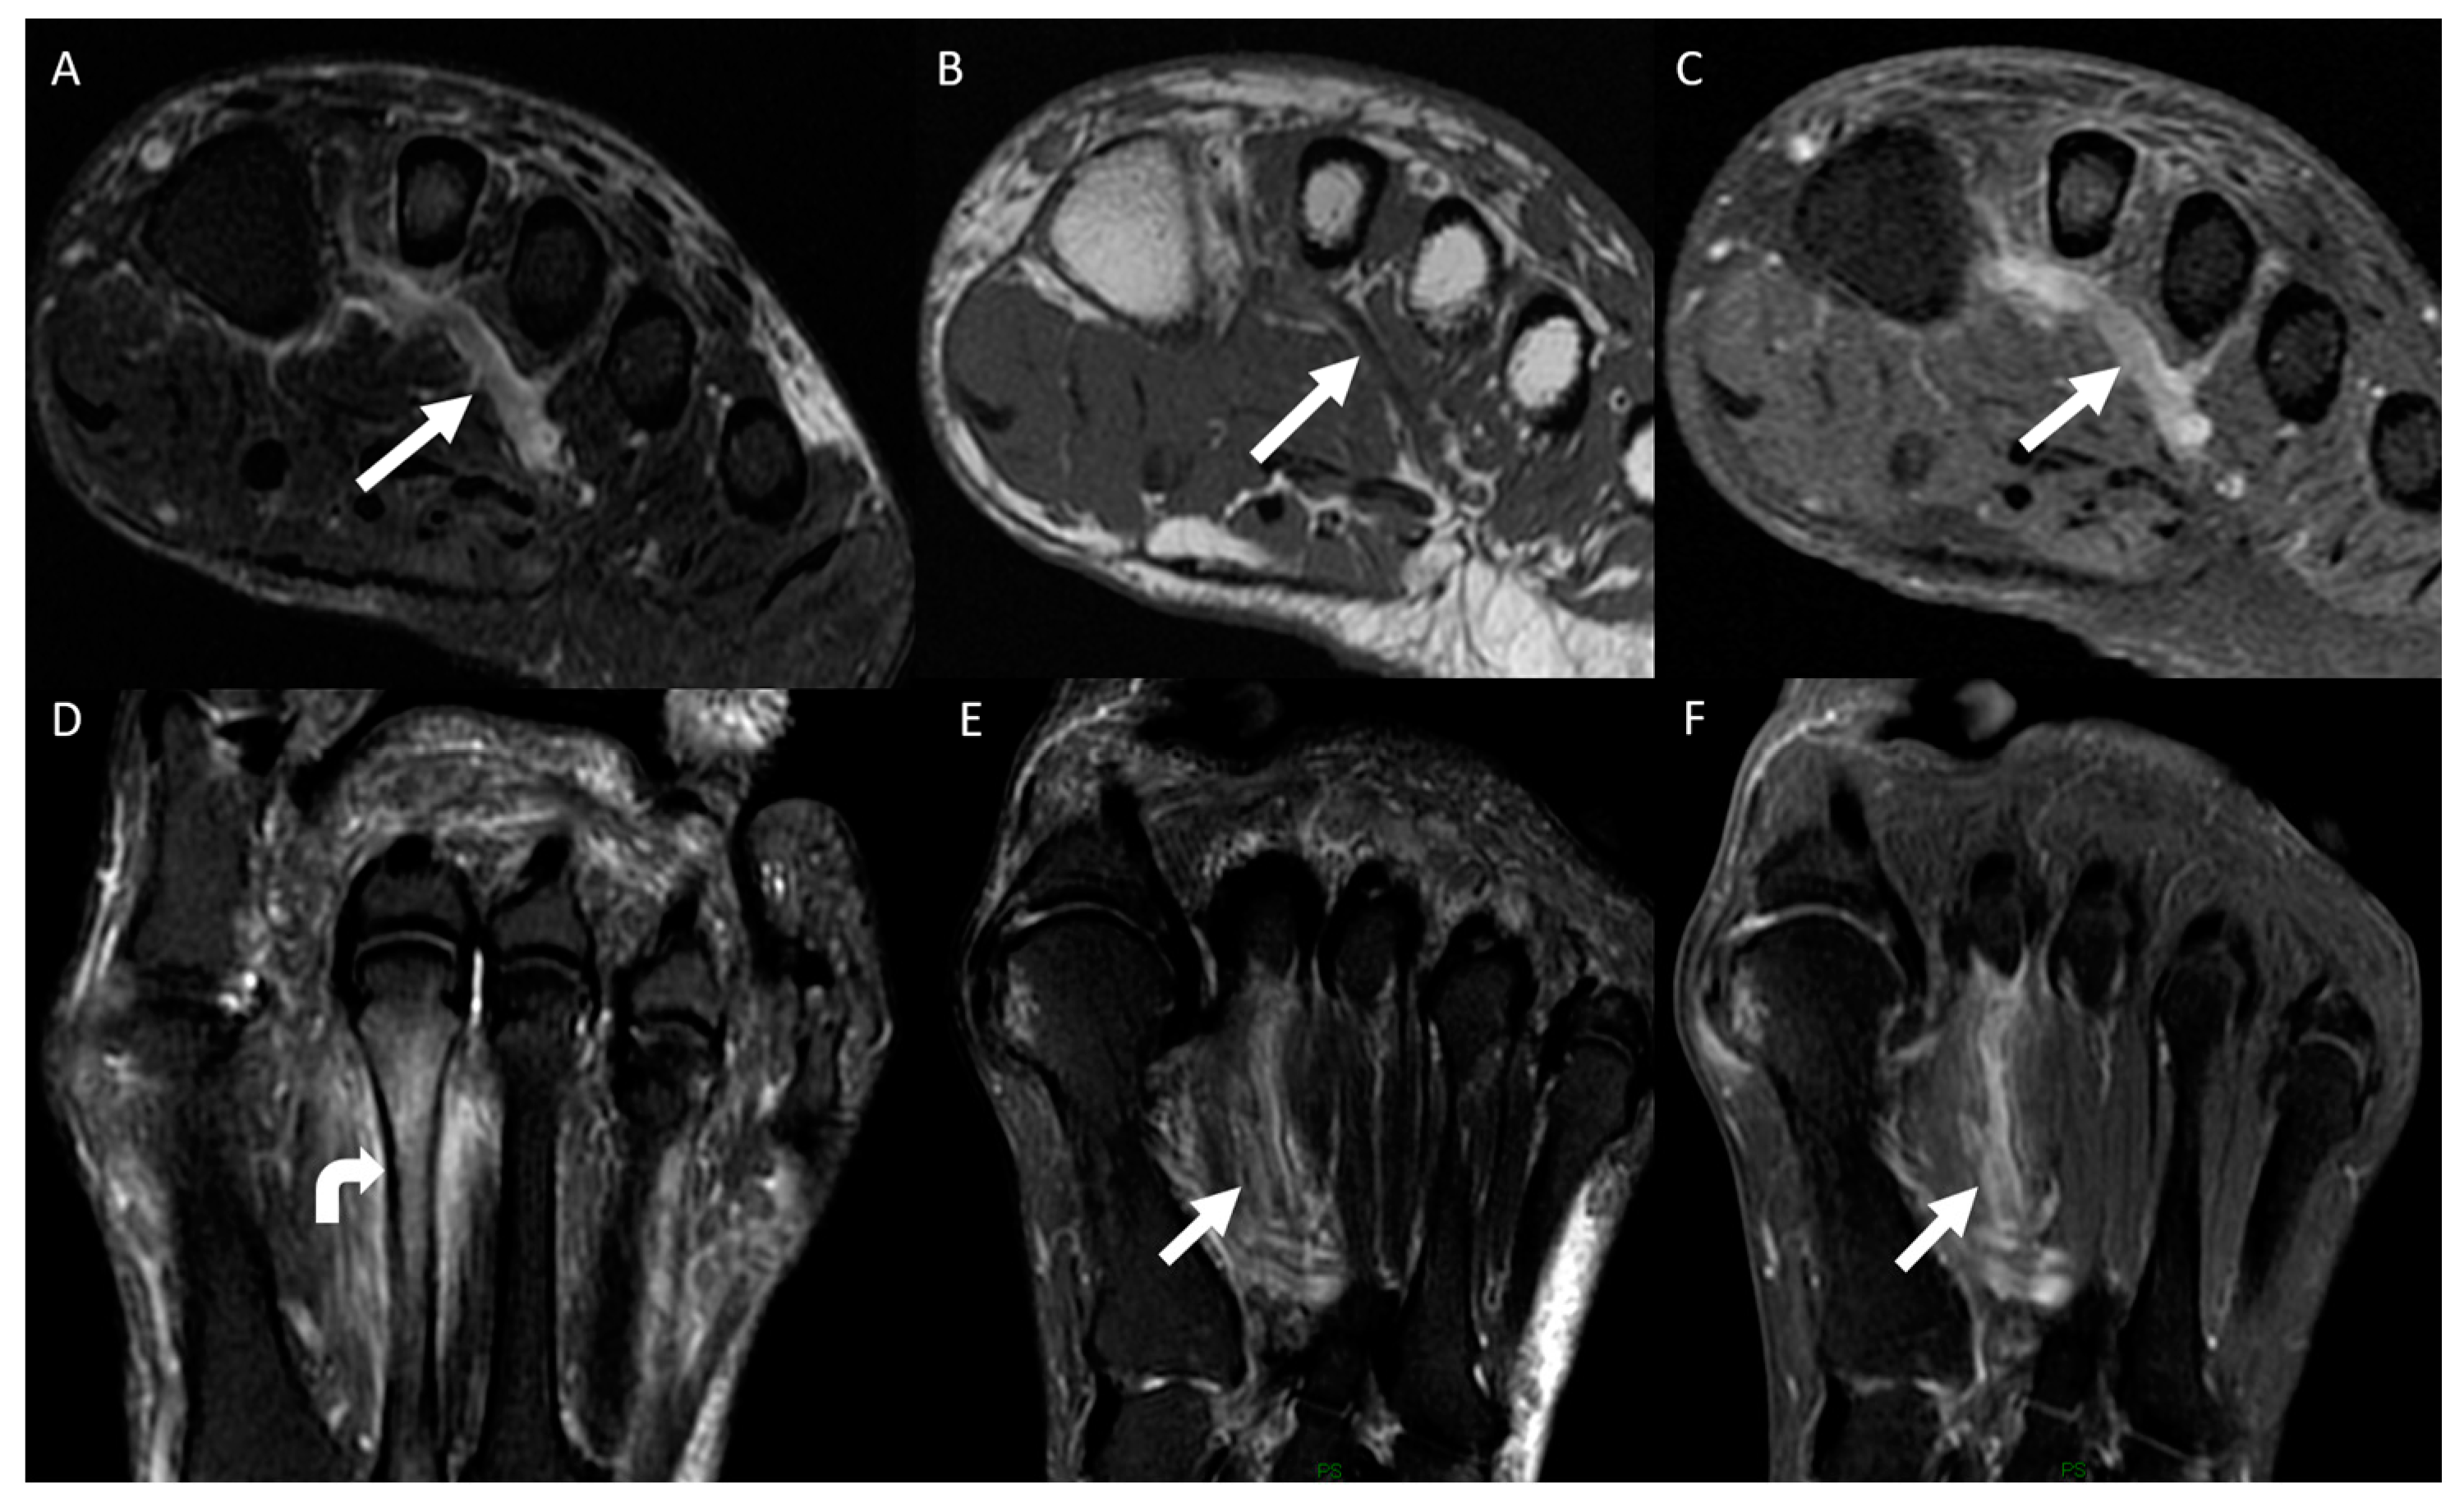

3.2. Distribution of MRI Findings